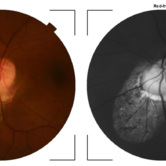

Chorioretinal coloboma involving disc and macula

Chorioretinal coloboma involving disc and macula

Mar 21 2022 by T. P . VIGNESH, MBBS,MS

Fundus photo of Right eye of a 55 year male patient revealing a fovea sparing well barraged chorioretinal coloboma involving the disc and the macula .

Photographer: Bharathi Singaravel

Imaging device: Zeiss Clarus

Condition/keywords: chorioretinal coloboma, coloboma of optic disc